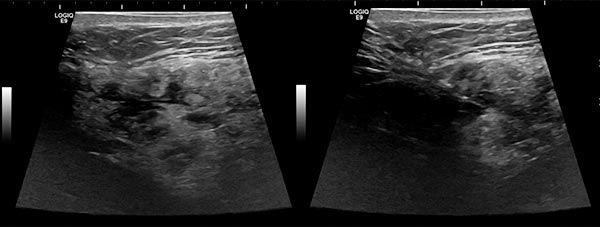

Ultraschallbilder (automatisch zusammengesetzte 2D-Darstellung) vor Sklerotherapie. Die initial echoärmeren Hohlräume der venösen Malformation werden durch die Inflammation, die durch die Sklerosierungstherapie induziert wird, verschlossen.